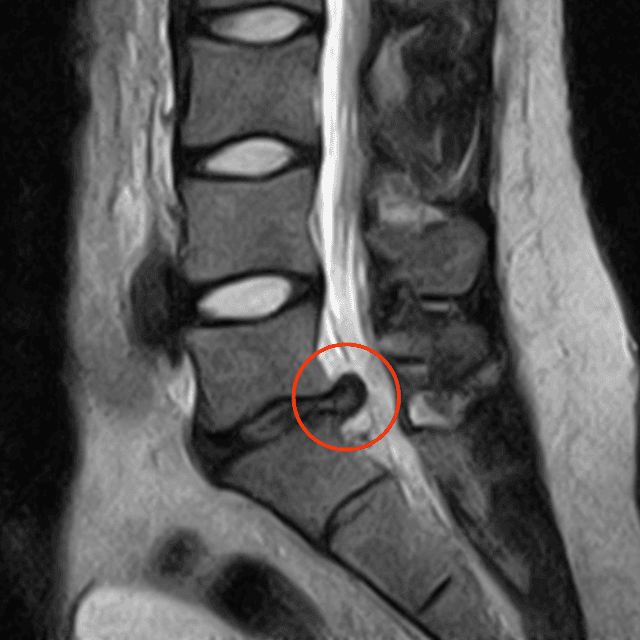

hernie discale

Hernie discale : Comment la soulager ?

L'hernie discale...